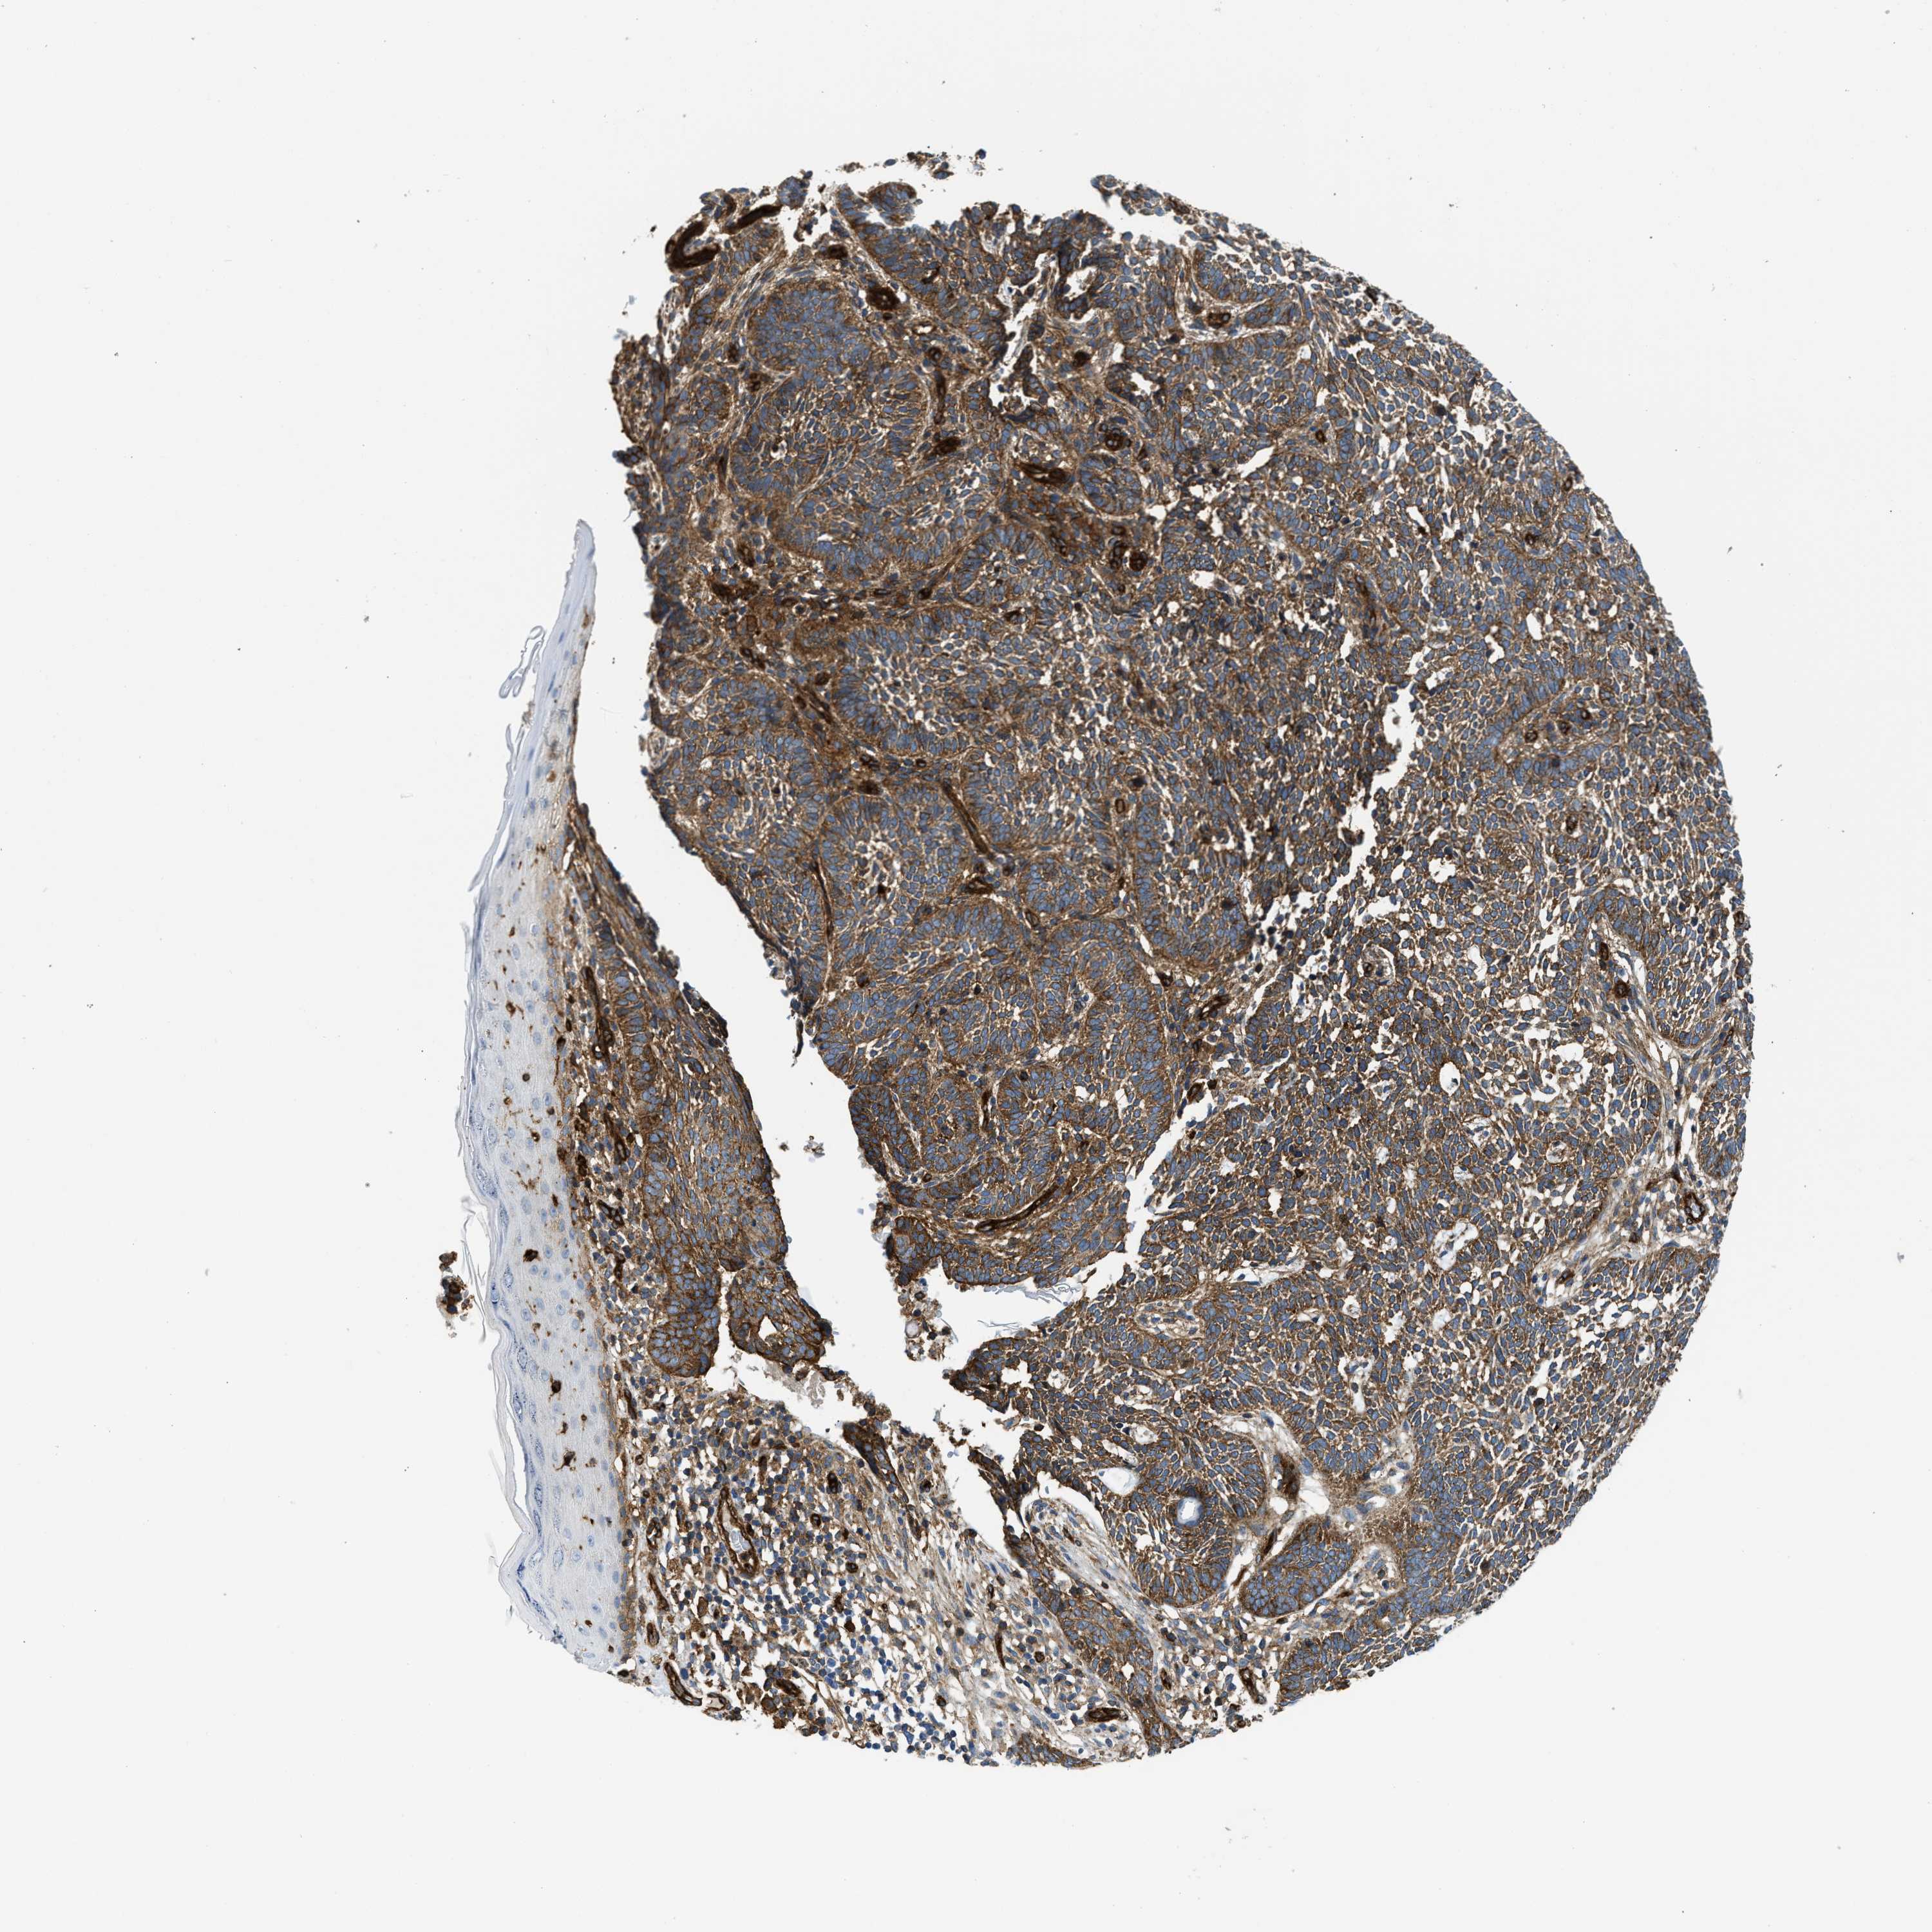

SKIN CANCER - Protein expressioni

A mouse-over function shows sample information and annotation data. Click on an image to view it in a full screen mode. Samples can be filtered based on level of antibody staining by selecting one or several of the following categories: high, medium, low and not detected. The assay and annotation is described here.

Antibody stainingi

Antibody staining in the annotated cell types in the current human tissue is reported as not detected, low, medium, or high, based on conventional immunohistochemistry profiling in selected tissues. This score is based on the combination of the staining intensity and fraction of stained cells.

Each image is clickable and will lead to virtual microscopy that enables deeper exploration of all samples and also displays staining intensity scores, fraction scores and subcellular localization as well as patient and tissue information for each sample.

Antibody CAB015334

Staining

High

Medium

Low

Not detected

Intensity

Strong

Moderate

Weak

Negative

Quantity

>75%

75%-25%

<25%

None

Location

Nuclear

Cytoplasmic/membranous

Cytoplasmic/membranous,nuclear

Squamous cell carcinoma, metastatic, NOS